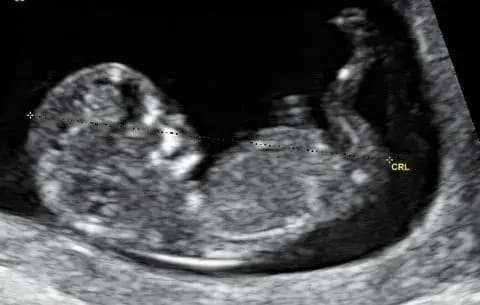

a baby human in the womb

"For you created my inmost being; you knit me together in my mother's womb."